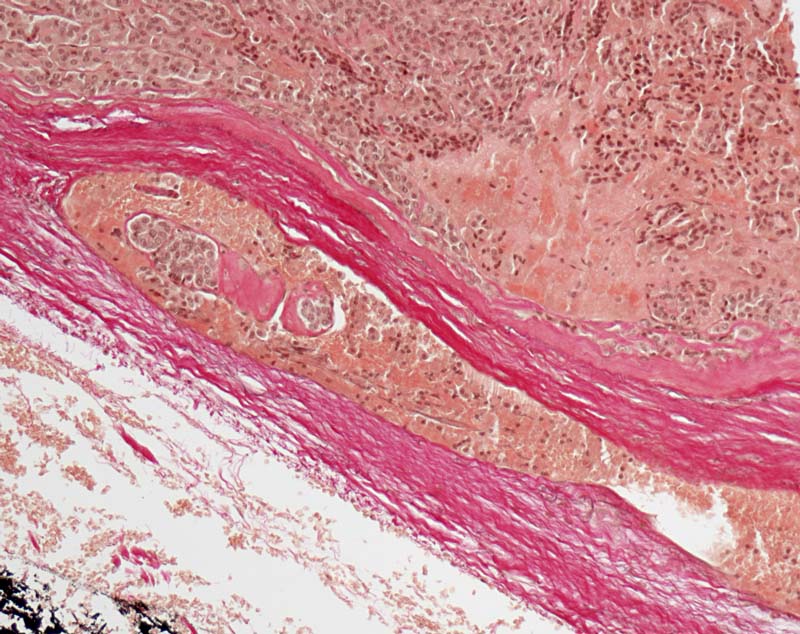

Follikuläres Schilddrüsenkarzinom: Gefässeinbruch

In einem endothelausgekleideten Gefäss der Tumorkapsel ist ein organisierter Tumorthrombus erkennbar.

Vor einem Jahr Schilddrüsenteilresektion wegen follikulärem Karzinom. Jetzt Resthyreoidektomie wegen Rezidiv.

Als eindeutige Gefässeinbrüche eines Schilddrüsenkarzinoms sind ausschliesslich Tumorthromben oder wandhaftende Tumorzellen in einem Gefäss in oder ausserhalb der Tumorkapsel anzusehen. Während der Verarbeitung des Operationspräparates werden oft einzelne Tumorzellen in Gefässlumina reingewischt. Solche reaktionslos innerhalb des Gefässlumens liegende Tumorzellen gelten nicht als Gefässeinbrüche (siehe Bild 8266).